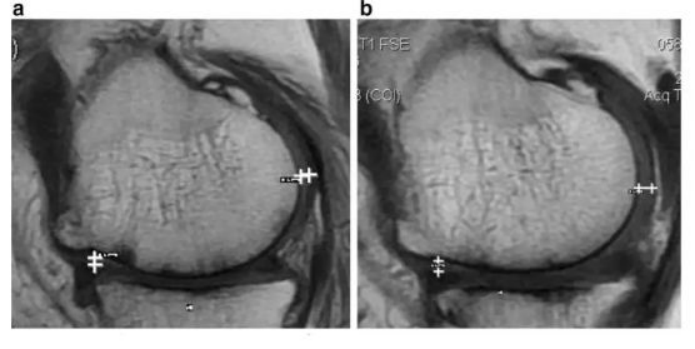

如上图所示,,,,左图为治疗前,,,,右图为治疗后,,,白色“+”处示意软骨增厚。。

image.png